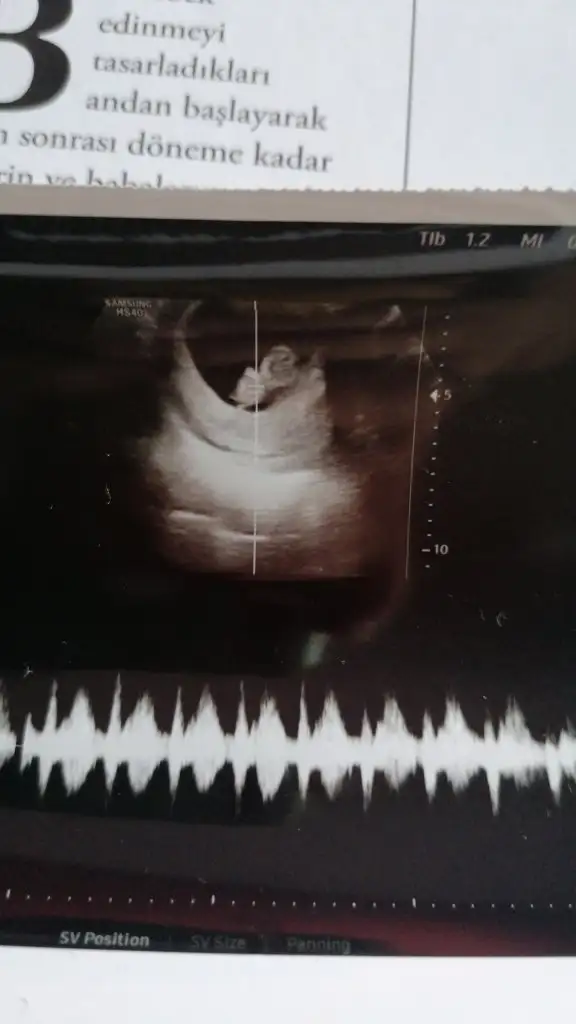

Birkac gun oynayabiliyorAhahah ne anladınızyurtdisindayim yarın ülkeye dönüyorum ve hemen yarına randevu aldım inşallah ilk kez bakacağım durum nedir diye:) 8 hafta mi oluyor? Ben 7 sanıyordum ya :)))